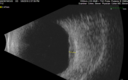

63 year old female She noticed a new thumbprint on her right eye with decreased vision March 10, 2019.  She waited a few days.  She was an eye institute where they said it was a cataract and scheduled for surgery.  She asked why if the cataracts are the same there was trouble with the one eye. He agreed and sent her to his retina specialist who noticed a problem and suggested a referral out. She has no health problems otherwise but has not been to a doctor lately.   VA OD: Dcc20/125 PHNI Ncc20/400 VA OS: Dcc20/50 PH20/32 NccJ5 IOP: TP: OD:23 OS:22 Time:15:56

Lung Cancer Metastasis to Right Eye372 views63 year old female with vision loss for 6 weeks. She had been scheduled for cataract surgery and then a tumor was found. She was ultimately diagnosed with lung cancer. Vision is 20/10000000